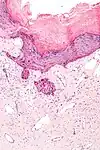

| Hematoxilina | Básica / Acidofílica | Tiñe núcleos, ácidos nucleicos y estructuras basofílicas (mitocondrias y ribosomas) en azul. | Tinción histológica general | ![]() |